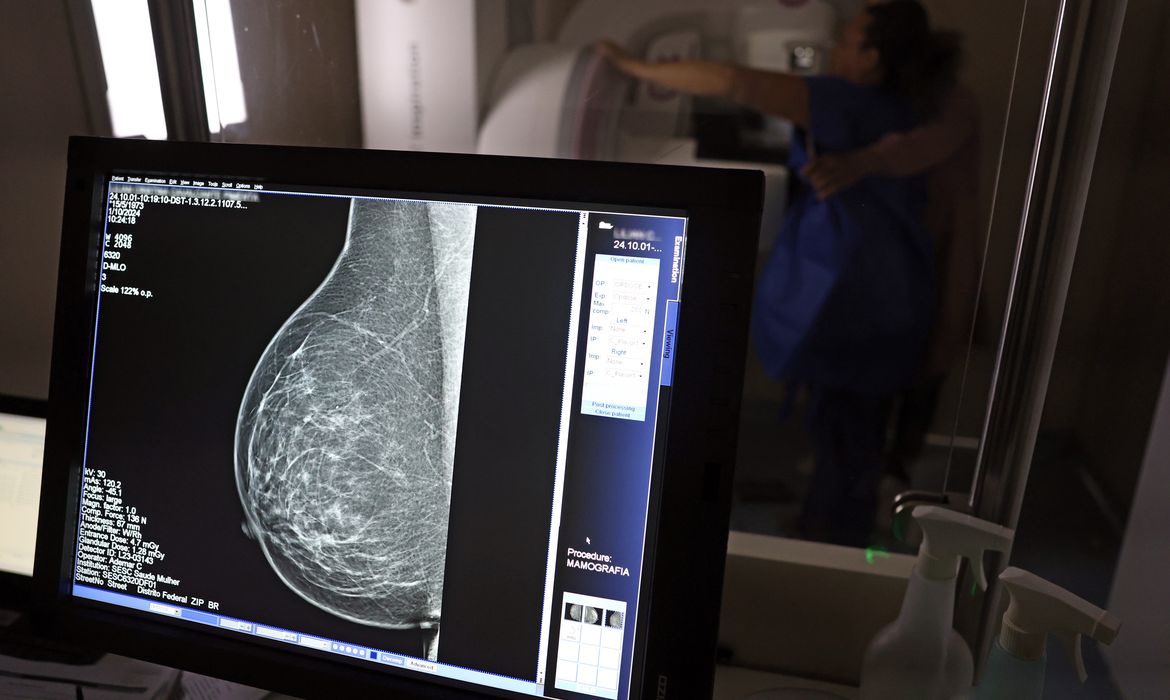

O resultado dessas barreiras é uma cobertura muito baixa: apenas 24% das mulheres no país fazem mamografia, bem abaixo dos 70% recomendados pela Organização Mundial da Saúde. Mesmo onde há mais equipamentos, como em São Paulo, a taxa não passa de 26%. Em setembro, o Ministério da Saúde ampliou as diretrizes de rastreamento, passando a recomendar exames anuais para mulheres de 40 a 49 anos, mesmo sem sintomas, e mantendo a indicação para mulheres de 50 a 74 anos, faixa que concentra maior risco. Mas, na prática, a detecção precoce ainda é inacessível para grande parte da população. Mais de 73 mil mulheres recebem o diagnóstico de câncer de mama por ano no Brasil, e o diagnóstico tardio ainda é um problema grave, especialmente entre mulheres negras e pardas.

A médica Ivie Braga de Paula enfatiza: a mamografia é o principal método para identificar tumores pequenos, assintomáticos, quando as chances de cura superam 95% em cinco anos, independentemente da agressividade do tumor. Esses resultados só são possíveis com acesso universal ao exame, independentemente da renda, raça ou local de residência. No contexto do Outubro Rosa, especialistas reforçam a necessidade de políticas públicas que garantam rastreamento equitativo, desburocratizem o agendamento de exames e ampliem a cobertura para populações vulneráveis. O desafio não é apenas aumentar o número de equipamentos, mas garantir que eles cheguem de fato a quem precisa, com qualidade, rapidez e equidade.